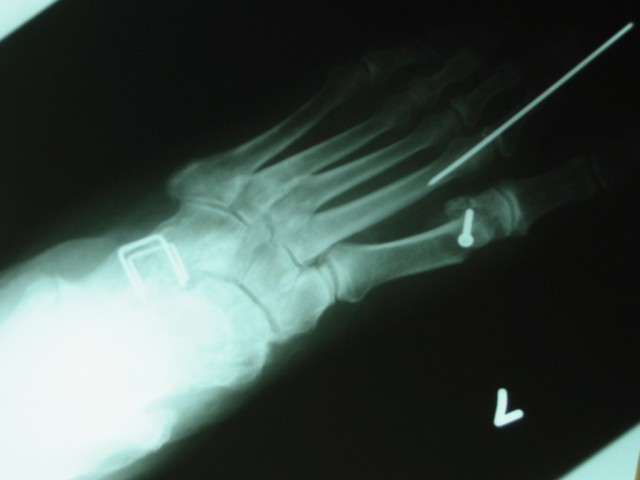

In Betty Lou's case, it included cutting and realigning the bone, holding it in place with a screw until it healed, and adjusting the tightness of a tendon and a joint capsule. Since the second toe had also been affected, it also was realigned and held in place by a really long pin. You can tell by the staples that this is the same foot that had the previous operation.